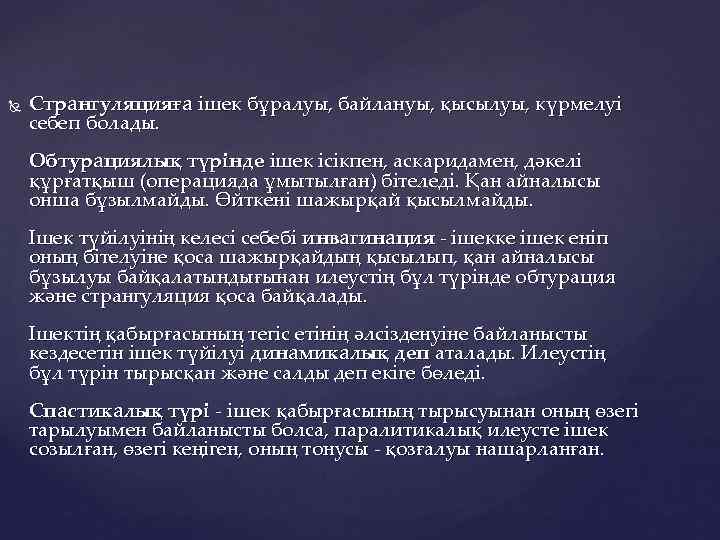

Странгуляцияға ішек бұралуы, байлануы, қысылуы, күрмелуі себеп болады. Обтурациялық түрінде ішек ісікпен, аскаридамен, дәкелі құрғатқыш (операцияда ұмытылған) бітеледі. Қан айналысы онша бұзылмайды. Өйткені шажырқай қысылмайды. Ішек түйілуінің келесі себебі инвагинация - ішекке ішек еніп оның бітелуіне қоса шажырқайдың қысылып, қан айналысы бұзылуы байқалатындығынан илеустің бұл түрінде обтурация және странгуляция қоса байқалады. Ішектің қабырғасының тегіс етінің әлсізденуіне байланысты кездесетін ішек түйілуі динамикалық деп аталады. Илеустің бұл түрін тырысқан және салды деп екіге бөледі. Спастикалық түрі - ішек қабырғасының тырысуынан оның өзегі тарылуымен байланысты болса, паралитикалық илеусте ішек созылған, өзегі кеңіген, оның тонусы - қозғалуы нашарланған.

Странгуляционная непроходимость кишечника Ущемление тяжом { Спастическая кишечная непроходимость {